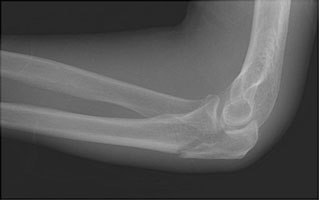

Olecranon Fracture

Olecranon fractures result from a direct fall onto a flexed elbow. As the triceps inserts upon the olecranon, most olecranon fractures tend to be displaced. These fractures are not generally comminuted.

- Click on the image for a larger versionALateral radiograph of the elbow. The typical appearance of an olecranon fracture. The triceps tendon has distracted the fracture fragments.